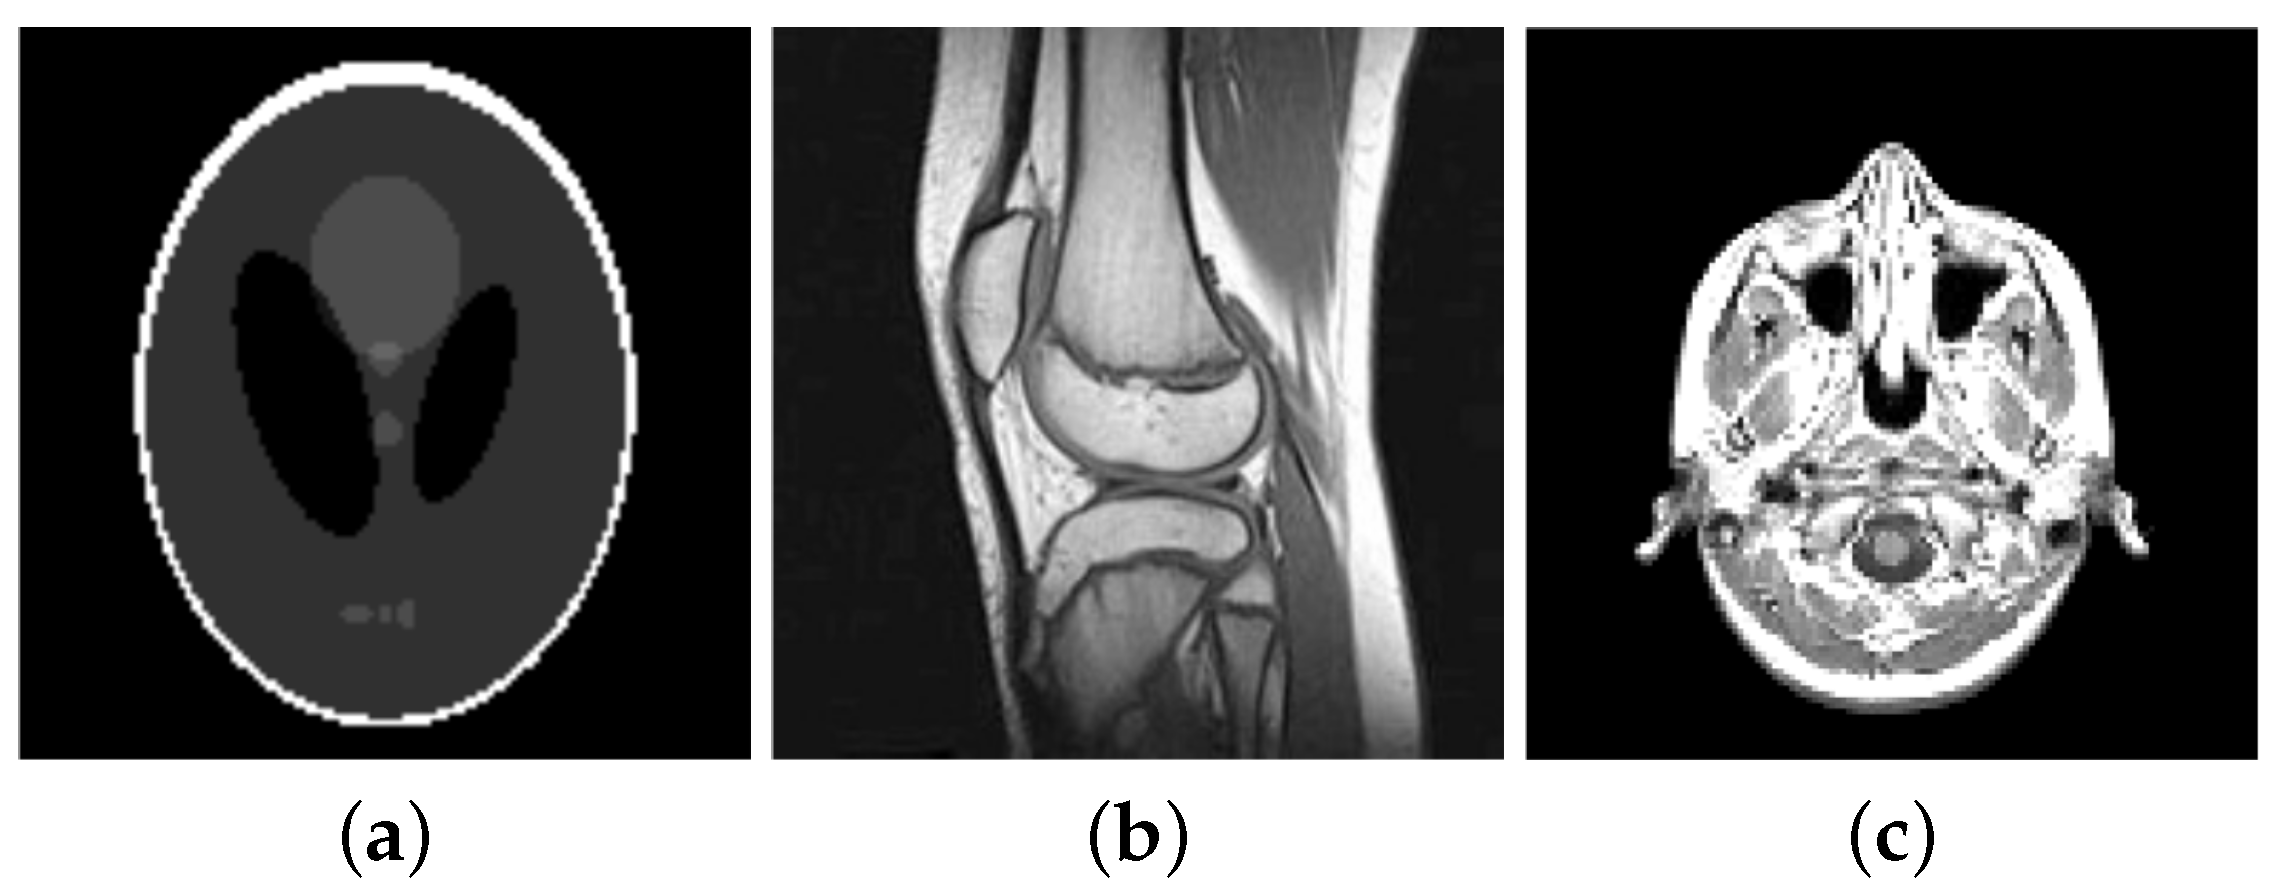

For our numerical studies we consider the images shown in Figure 1 of size 256 × 256 pixels and in Figure 2. The image intensity range of all original images considered in this paper is , i.e., and . Our proposed algorithms automatically transform this images into the dynamic range , here with . That is, let be the original image before any corruption, then . Moreover, the solution generated by the semi-smooth Newton method is afterwards back-transformed, i.e., the generated solution is transformed to . Note that is not necessarily in , except .

Figure 2.

Original images (a) Shepp-Logan phantom of size pixels (b) knee of size pixels (c) slice of a human brain of size pixels.

In our experiments we consider the images of Figure 2, transformed to its Fourier frequencies. As already mentioned, we sample the frequencies along 32 radial lines and add some Gaussian noise with zero mean and standard deviation . In particular, we consider different noise-levels, i.e., . We reconstruct the obtained data via the pAPS- and pLATV-algorithm by using the semi-smooth Newton method first with (no box-constraint) and then with (with box-constraint). In Table 13 we collect our findings. We observe that the pLATV-algorithm seems not to be suitable for this task, since it is generating inferior results. For scalar we observe as before, that a slight improvement with respect to PSNR and MSSIM is expectable when a box-constraint is used. In Figure 13 we present the reconstructions generated by the considered algorithms for a particular example, demonstrating the visual behavior of the methods.

6.3.6. Reconstruction from Sampled Radon-Data

In computerized tomography instead of a Fourier-transform a Radon-transform is used in order to obtain a visual image from the measured physical data. Also here the data is obtained along radial lines. Here we consider the Shepp-Logan phantom, see Figure 14a, and a slice of a body, see Figure 15a. The sinogram in Figure 14a and Figure 15b are obtained by sampling along 30 and 60 radial lines, respectively, Note, that the sinogram is in general noisy. Here the data is corrupted by Gaussian white noise with standard deviation , whereby for the data of the Shepp-Logan phantom and for the data of the slice of the head. Using the inverse Radon-transform we obtain Figure 16a,b, which is obviously a suboptimal reconstruction. A more sophisticated approach utilizes the -TV model which yields the reconstruction depicted in Figure 16b,e, where we use the pAPS-algorithm and the proposed primal-dual algorithm with . However, since an image can be assumed to have non-negative values, we may incorporate a non-negativity constraint via the box-constrained -TV model yielding the result in Figure 16c,f, which is a much better reconstruction. Also here the parameter is automatically computed by the pAPS-algorithm and the non-negativity constraint is incorporated by setting in the semi-smooth Newton method. In order to compute the Radon-matrix in our experiments we used the FlexBox [52].

Figure 16.

Reconstruction from noisy data. (a) Inverse Radon-transform (PSNR: 29.08; MSSIM: 0.3906); (b) -TV (PSNR: 29.14; MSSIM: 0.4051); (c) Box-constrained -TV (PSNR: 33.31; MSSIM: 0.6128); (d) Inverse Radon-transform (PSNR: 31.75; MSSIM: 0.3699); (e) -TV (PSNR: 32.16; MSSIM: 0.3682); (f) Box-constrained -TV (PSNR: 36.08; MSSIM: 0.5856).